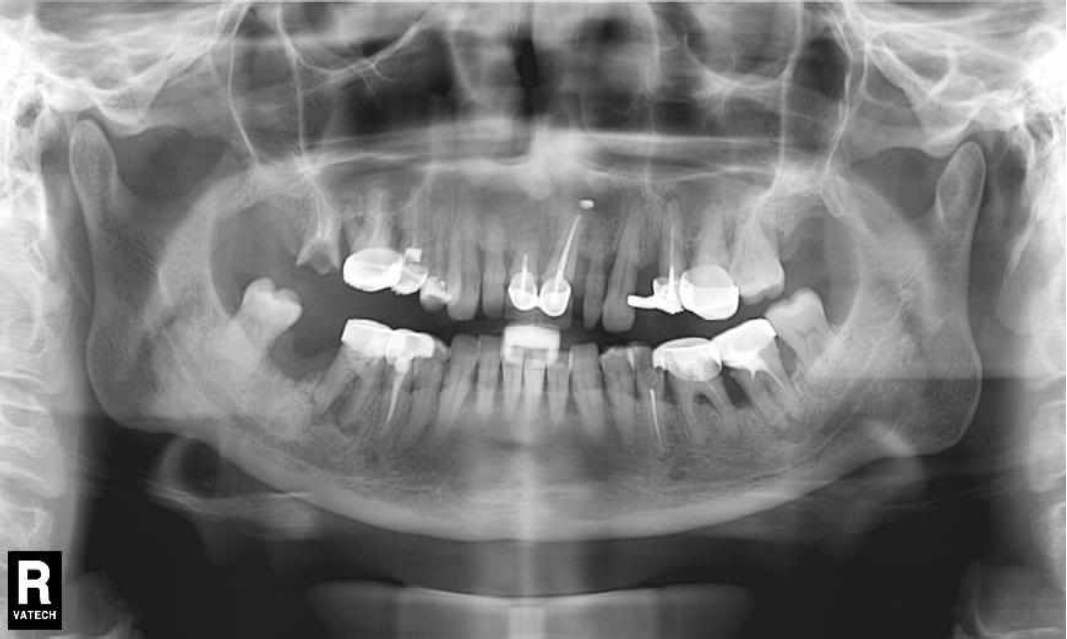

Ранее у пародонтолога не наблюдалась. При осмотре выявлены: неудовлетворительная индивидуальная гигиена полости рта, пародонтальные карманы до 7 мм, обильная кровоточивость и гноетечение из пародонтальных карманов, подвижность зубов 4.2, 4.1, 3.1, 3.2 II степени, обильные над- и поддесневые зубные отложения (рис. 1). На ортопантомограме отмечается резорбция костной ткани до ½ длины корня, очаги остеопороза (рис. 2). Пациенту был поставлен диагноз хронический генерализованный пародонтит тяжелой степени тяжести. При осмотре была составлена пародонтограмма с использованием компьютерного зондирования (рис. 3).

Рис. 2. Ортопантомограмма исходной ситуации пациента состояния полости рта

После проведения осмотра пациента приступаем к рентгенологическому исследованию, которое является дополнительным методом в диагностике заболеваний пародонта, но необходимо для постановки окончательного диагноза. Для этой цели используют полную серию прицельных рентгенограмм или КЛКТ.